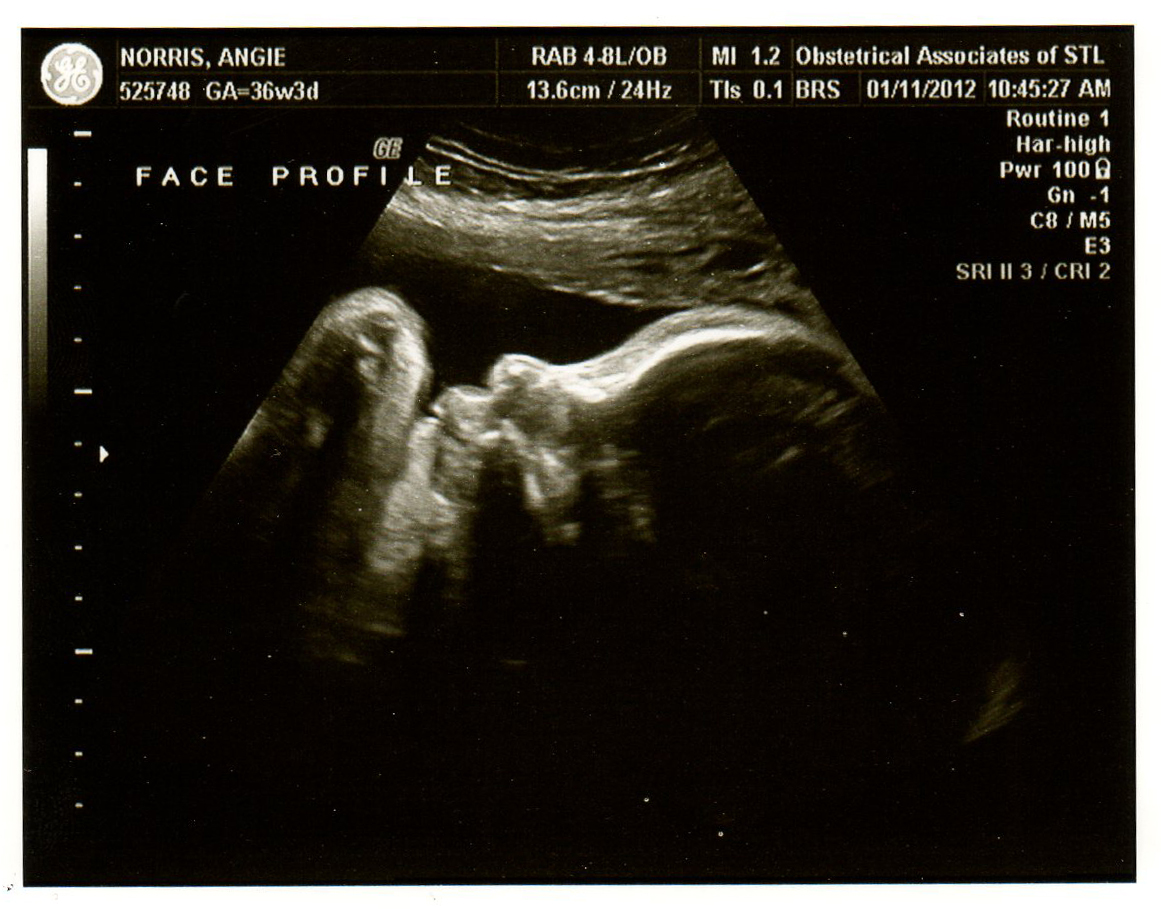

Went to the doctor on Wednesday and had an ultrasound. Are these pictures so cute? So unbelievable how we can see little Lexi's face...wow. She is measuring at about 5 lbs which seems to be the same as with Tia, so I just have small babies. Everything looks good though. Everything is the same from last week in regards to dialation and effacement. I feel really good and all seems well with baby. If he induces me a week before, then I have about 2 and a half weeks left to go...it will be here before we know it!